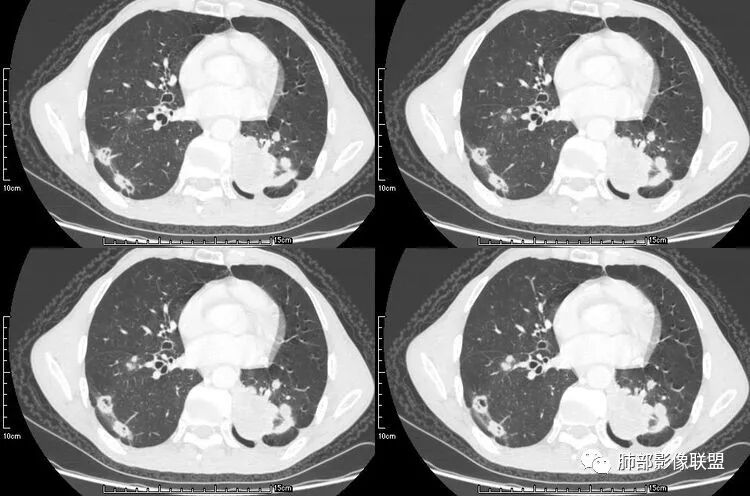

患者老年男性,咳嗽、咳痰、痰中带血伴胸闷2月余。长期大量吸烟史。查肝肾功能、血糖、血脂、心肌酶、电解质、血沉、C反应蛋白、抗“O”、类风湿因子、抗核抗体谱无明显异常。肿瘤标志物提示NSE、CYFRA21-1稍升高。胸部CT:肺气肿背景,左肺下叶后基底段不规则肿块影,见支气管截断,内见大片状低密度区及部分血管影,增强轻度强化,远端空洞形成。双肺多发不规则实性结节影、见毛刺、胸膜牵拉及血管集束,结节内见空洞形成,部分可见血管影,多位于胸膜下。双肺见多发肺大泡。综合考虑左下肺恶性病变并双肺转移。鳞癌或淋巴瘤可能。鉴别血管炎性病变及真菌感染。

go and see:叶间裂也是多发结节

无发热,其他慢性细菌先不考虑,有的低毒的,但是结节形态还是比较不规则的,分布也是比较随机,更像原发病灶。真菌方面,结节没有融合,坏死也是液化坏死,不符合隐球菌,曲霉不符合IPA,慢性吸入的也少见。结核没有树丫,不考虑。鉴别主要是GPA,和肺癌。GPA不支持点是皮肤,肾脏没有累及,ANCA不支持。。。肺癌主要是腺癌和鳞癌转移。比较支持的是淋巴结肿大,和左下肺的主病灶,支气管堵塞和异常强化。还有分叶,局部膨隆。可以建议支气管镜检测。

@毛勤香 柳州龙潭医院影像  转移结节很多都有毛刺,有收缩力,而且叶间裂多个结节(符合黄勇老师六个核桃理论)

本病例左肺下叶肿块,有深分叶、毛刺、胸膜牵拉凹陷、支气管截断及纵隔内淋巴结肿大等征象,都均支持病灶为恶性,如腺癌,而且叶间裂的多发结节也提示是腺癌来源可能大;双肺多发结节、肿块,大部分病灶有分叶、毛刺及胸膜凹陷的恶性征象,与原发肿瘤本身的性质有关,所以应该与左肺下叶肿块同源,而且双肺多发病灶内空洞也具有多样性;